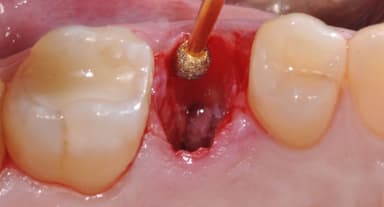

– Thực hiện nhổ răng khôn: Hiện tại, Piezotome là công nghệ nhổ răng khôn được nhiều bệnh nhân lựa chọn nhất. Công nghệ này sử dụng sóng siêu âm để bóc tách hệ thống dây chằng khỏi chân răng. Không còn được nâng đỡ bởi hệ thống dây chằng, răng khôn dễ dàng được nha sĩ loại bỏ, đảm bảo không phát sinh tổn thương lan tỏa. Với cơ chế hoạt động đó, công nghệ nhổ răng khôn Piezotome sở hữu nhiều ưu điểm vượt trội như: Thời gian thực hiện nhanh (chỉ 7 – 15 phút); không đau; hạn chế chảy máu; giảm sưng nề; hạn chế biến chứng;…